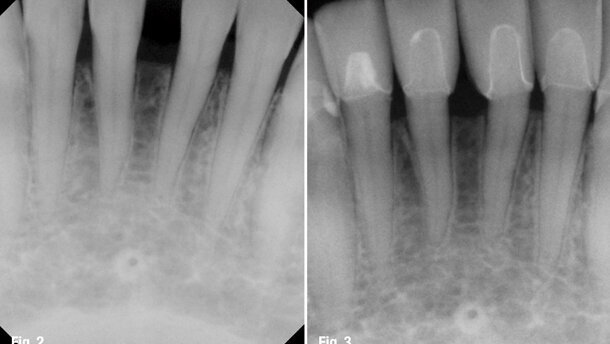

The periodontitis and bone loss were partially due to a traumatic bite that improperly distributed the occlusal forces laterally rather than perpendicularly so that the loading forces were forcing the lower anteriors to splay (Figs. 2–5).

The patient received 28 units made of a pressible ceramic (IPS Empress Esthetic, Ivoclar Vivadent). The zirconium bridge was not removed as it was new, in good condition and the occlusion and stability could be added directly on to it by building it up. The patient’s vertical dimension was permanently raised with the prosthetics throughout, to compensate for the collapsed occlusion. This altered the facial structure and smile by enhancing how the teeth, lips gums and face work together as a whole (Figs. 8–10). Also, the patient benefited from a healthier oral cavity. Two years later, there is bone regeneration in the lower anteriors (a benefit of LANAP), the pockets have disappeared and the patient is enjoying occlusal health with aesthetic accompaniment.